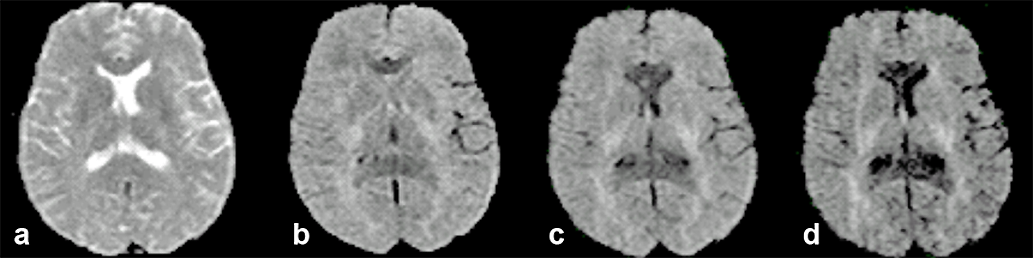

Figure 11-10 gives an example of how diffusion influences contrast and its de­pen­d­en­ce upon gradient direction.

Figura 11-10:

Transverse, increasingly diffusion-weighted images.

(a) b = 0 s/mm² (no diffusion weighting); (b) b = 600 s/mm²; (c) b = 900 s/mm²; (d) b = 1200 s/mm².

Regions with a high diffusion gradient show low signal intensity, regions with low or ob­­struct­ed diffusion are brighter. This is the reason for contrast enhancement in dif­fu­­sion weighted imaging, allowing for instance the early depiction of brain in­farc­­tion.

Appreciation of the contrast enhance­ment always requires the comparison of at least two images with dif­fe­rent b-values.